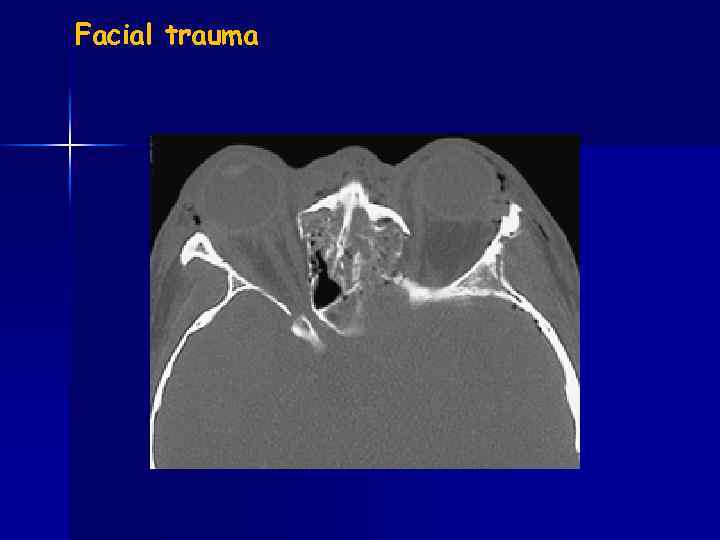

Facial trauma Le Fort fracture

Facial trauma

Facial trauma blow-out fracture